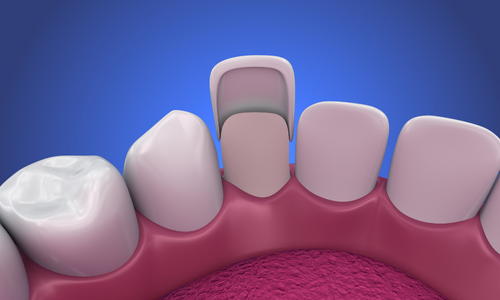

Bununla birlikte, teknolojiye ve yenilikçi uygulamalara verdiğimiz önem de bizi farklı kılan unsurlardan biridir. Tosun Diş

Kliniği olarak, en son diş tedavisi tekniklerini ve ekipmanlarını kullanarak, hastalarımıza en iyi sonuçları sağlamak için

sürekli olarak kendimizi güncelliyoruz. Bu sayede, güvenilir, etkili ve konforlu bir tedavi deneyimi sunarak fark

yaratıyoruz.